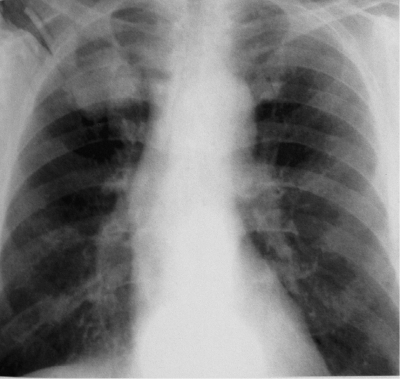

При хроническом диссеминированном туберкулёзе лёгких изменения на рентгенограмме отличаются большим разнообразием. Характерным признаком считают субтотальную или тотальную, относительно симметричную полиморфную очаговую диссеминацию (рис. 18-28). Множественные очаговые тени имеют различную величину, форму и интенсивность, что обусловлено разной давностью их образования. В верхних и средних отделах лёгких очаговые тени более крупные, их значительно больше, чем в нижних. Наклонности к слиянию очагов нет. Симметричность изменений может быть нарушена по мере появления новых высыпаний. У некоторых больных в обоих лёгких видны полости распада в виде тонкостенных кольцевидных теней с чёткими внутренними и наружными контурами - так выглядят штампованные, или очковые, каверны (рис. 18-29).

Рис. 18-28. Хронический диссеминированный туберкулёз. Полиморфная диссеминация в лёгких. Обзорная прямая рентгенограмма.

В верхних отделах обоих лёгких лёгочный рисунок усилен, деформирован и имеет сетчато-ячеистый характер в связи с выраженным интерстициальным фиброзом. Хорошо видны двусторонние кортико-апикальные плевральные наслоения (шварты). В базальных отделах лёгочный рисунок обеднён, прозрачность лёгочной ткани повышена из-за викарной эмфиземы. В связи с фиброзом и уменьшением объёма верхних долей тени корней лёгких симметрично подтянуты вверх (симптом "плакучей ивы"). Тень сердца на рентгенограмме имеет срединное положение ("капельное сердце"), а его поперечный размер в области крупных сосудов сужен.